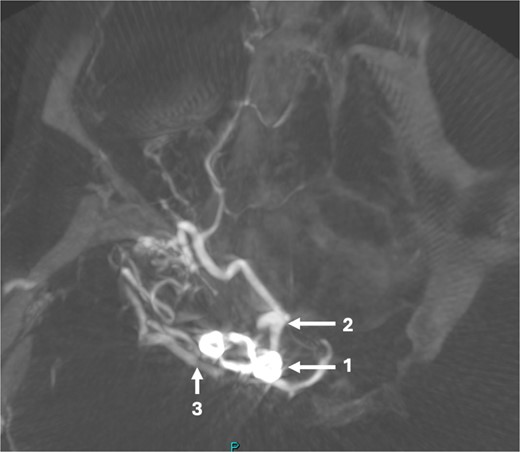

A 43-year-old lady, with known hypertension, presented with severe and sudden onset headache in 2010. Initial computed tomography (CT) head confirmed a diffuse subarachnoid haemorrhage (images not available) and a subsequent CT angiogram showed a right supraclinoid internal carotid artery (ICA) aneurysm (Fig. 1). CT Angiogram also showed an unruptured left posterior communicating which was thought not to be related to this patient’s presentation and managed conservatively with serial imaging. The patient underwent emergency craniotomy on the same day where an encircling Sundt clip was applied to secure the aneurysm. She made a full neurological recovery and was discharged from hospital. Post-operative day 1 CT angiogram demonstrated relatively normal calibre of the right A1 portion of anterior cerebral artery (ACA) and M1 portion of middle cerebral artery (MCA), in the terminal carotid region (Fig. 2).

Axial post-operative CT angiogram demonstrating the (1) encircling clip occlusion of the terminal internal carotid artery aneurysm with a relatively normal calibre of (2) A1 and, (3) M1.